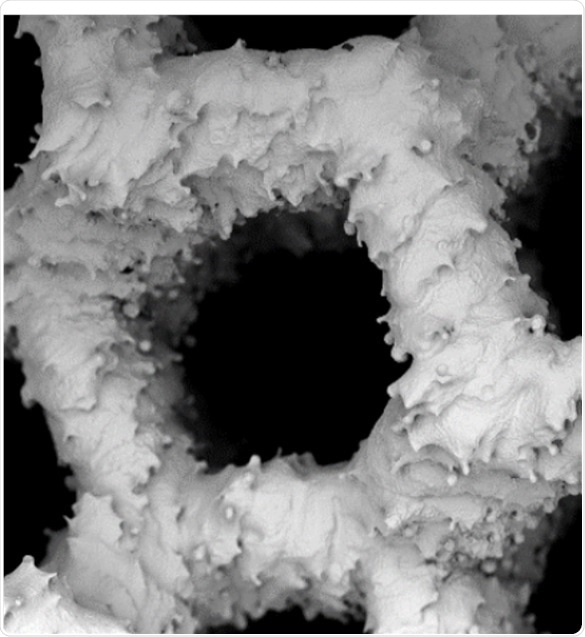

The laboratory used a SEM for this comparison, wherein the growth of human osteoblast (bone matrix cells) on BioOssⓇ, a human-like synthetic bone matrix, and on allogeneic bones after 1 week and then 3 weeks of culture, were compared. These images help concluding that the performance of the two materials is equal and confirm the efficiency of highly-processed synthetic grafts.

Figure 1. Top row: examples of SEM of human osteoblasts seeded on cancellous bone (ACB) after 1 week of cultivation, showing embedded cells in a bone typical extracellular matrix (image magnification 555x and 1300x as indicated). Lower row: After 3 weeks of cultivation an extensive growth of the osteoblasts could be observed on the surface on BioOss® (image magnification 600x and 2840x as indicated). Images adapted1.